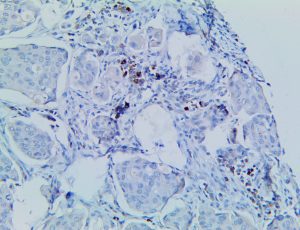

It is the ICU physician who is most likely to witness one of the deadliest manifestations of the abnormal immunological response, the cytokine storm syndrome (CSS). This response is also referred to by some as the cytokine release syndrome (CRS). CSS is characterized by continuous activation and expansion of macrophage and lymphocyte populations, which secrete large amounts of cytokines, causing the cytokine storm. This massive cytokine release is akin to hemophagocytic lymphohistiocytosis (HLH) disease, a syndrome characterized by initial unchecked and persistent activation of cytotoxic T lymphocytes and NK cells.

Clinical and laboratory manifestations of HLH include fever, enlarged liver and/or spleen, neurologic dysfunction, coagulopathy, liver dysfunction, cytopenias (i.e., low levels of erythrocytes, leukocytes, and/or platelets), hypertriglyceridemia, hyperferritinemia, hemophagocytosis, and eventually diminished NK cell activity as the immune system becomes progressively paralyzed. HLH can be familial (primary HLH) or secondary to another disease process (sHLH), such as rheumatic disease, in which it is referred to as macrophage activation syndrome (MAS, characterized by elevated ferritin).